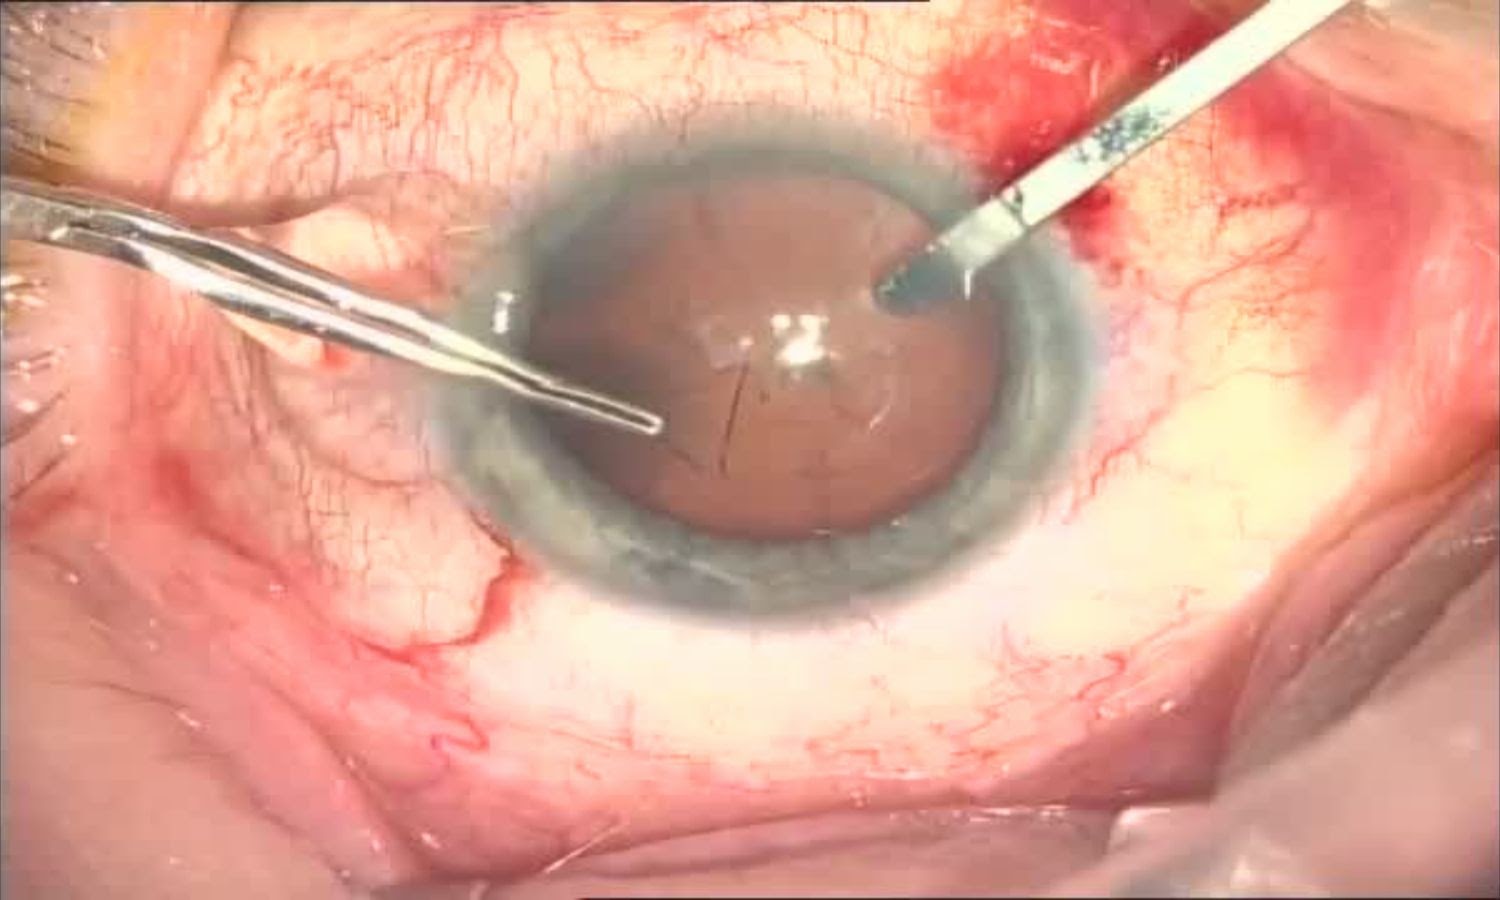

Первым инструментом в руках хирурга во время операции становится алмазный офтальмологический нож (он же скальпель или копьё). Дорогая и чертовский острая штука с алмазной заточкой, а то и вовсе из цельного синтетического алмаза. Сегодня хорошей заменой служат одноразовые ножи-кератомы. Ими делается два небольших (менее 1 мм) ступенчатых входа-прокола в роговице, через которые происходят манипуляции и один основной вход в 1,8 мм — он нужен для введения ультразвуковой иглы и через него же в дальнейшем будет установлена ИОЛ.

Далее этап удаления хрусталика. Чтобы добраться до его внутренностей (ядра и коры) хирург моделирует круглое отверстие в хрусталике в виде круга вручную или специальным лазером. Эта процедура называется круговым капсулорексисом.

Представьте, рукой хирург делает ровный круг диаметром 6—7 мм, вскрывая капсулу толщиной 30 микрон (тоньше человеческого волоса).

Круговой капсулорексис готов:

Форма, размеры и завершение капсулорексиса — очень важная часть операции. Если хирург неумелый, то порвать капсулу можно в два счёта и это сделает операцию осложнённой, а в некоторых случаях её даже невозможно закончить факоэмульсификацией.